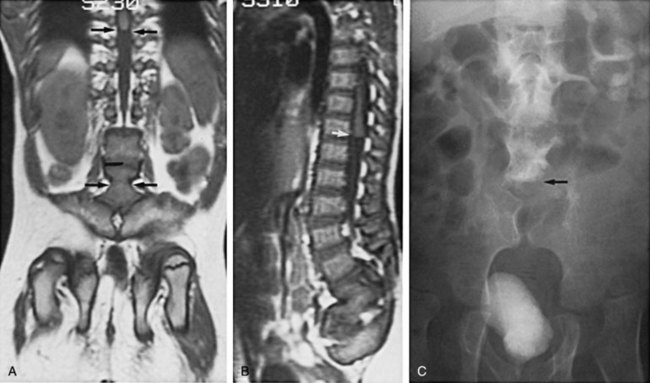

In addition to MRI studies (Tracey and Hanigan, 1990), urodynamic testing including EMG of the external urethral sphincter should be performed in every child who has a questionable cutaneous or bony abnormality of the lower spine, especially if there is a radiologic abnormality of the spinal cord (Packer et al, 1986; Campobasso et al, 1988; Hall et al, 1988; Meyrat et al, 2003). This test provides the most accurate measure of sacral spinal cord function at diagnosis and provides a basis for comparison with subsequent studies when the children are either operated on or carefully observed. In children younger than 3 months of age the vertebral bones have not ossified; thus a window of opportunity exists for ultrasonography to be a useful screening tool in visualizing the spinal canal (Fig. 128–15) (Raghavendra et al, 1983; Scheible et al, 1983). At this age there is good correlation between the ultrasound imaging and MRI findings; however, if a spinal cord abnormality is identified the latter provides for a better definition of the spinal cord lesion. Consequently, ultrasonography should not be used as the definitive imaging modality (Hughes et al, 2003). Older children with an occult spinal cord lesion may have urologic symptoms in 20% of cases (Hsieh et al, 2006), and 50% to 60% may have abnormal urodynamic findings preoperatively (Geurra et al, 2006). Resolution of the abnormal urodynamic parameters is noted in 50% to 60% of cases after detethering (Hseih et al, 2006; Geurra et al, 2006). Therefore, urodynamic study is recommended for all children with an occult spinal dysraphism before and after spinal cord detethering procedures.

Figure 128–15 A, During the first few months of life, ultrasonography can clearly demonstrate intravertebral anatomy because the posterior arches have not completely ossified. Note that the spinal cord along with its central canal is displaced anteriorly (white arrows) beginning at L3 because of an intradural lipoma. B, The MR image is juxtaposed to confirm the ultrasound findings. The longitudinal white intraspinal mass (black arrows) is the lipoma; the longitudinal gray mass is the spinal cord.